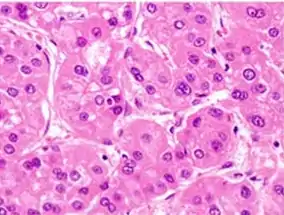

Microscopically, the four architectural and cytological types (patterns) of hepatocellular carcinoma are: fibrolamellar, pseudoglandular (adenoid), pleomorphic (giant cell), and clear cell. In well-differentiated forms, tumor cells resemble hepatocytes, form trabeculae, cords, and nests, and may contain bile pigment in the cytoplasm. In poorly differentiated forms, malignant epithelial cells are discohesive, pleomorphic, anaplastic, and giant. The tumor has a scant stroma and central necrosis because of the poor vascularization.[39] A fifth form – lymphoepithelioma like hepatocellular carcinoma – has also been described.[40][41]

Micrograph of hepatocellular carcinoma. Liver biopsy. Well-differentiated HCC

Well-differentiated HCC Moderately differentiated HCC.

Moderately differentiated HCC. Poorly differentiated HCC